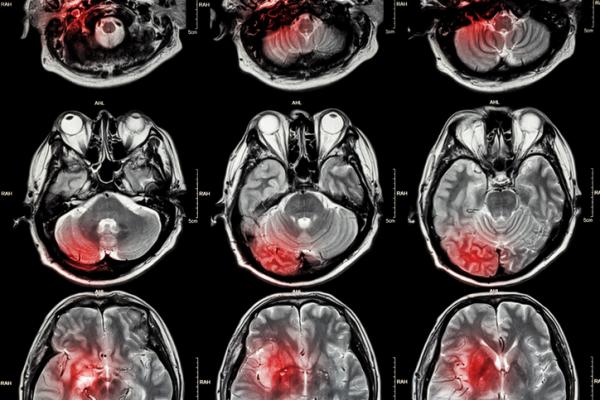

Professor Vibhudutta Awasthi, Ph.D., Associate Dean of Research, inventor and co-inventor Hailey Houson, M.D., at the University of Oklahoma said, “An 18F-FGA imaging agent for necrosis can revolutionize a diagnostic workup of many human diseases where tissue necrosis occurs as part of the pathology. This tracer enables use of high resolution, high sensitivity PET, to detect myocardial infarction and brain stroke. We are delighted to hear about MTTI’s effort to commercialize this technology.”

“The search for agents that could image necroses, without accumulating in living tissue, has been going on for decades. This innovative 18F PET tracer is specific for dead cells. It is also ideal for monitoring rapid tumor response to radiation and drug treatment. We’re excited for this discovery and look forward to advancing this molecule to clinic,” said Chris Pak, President and CEO of MTTI.